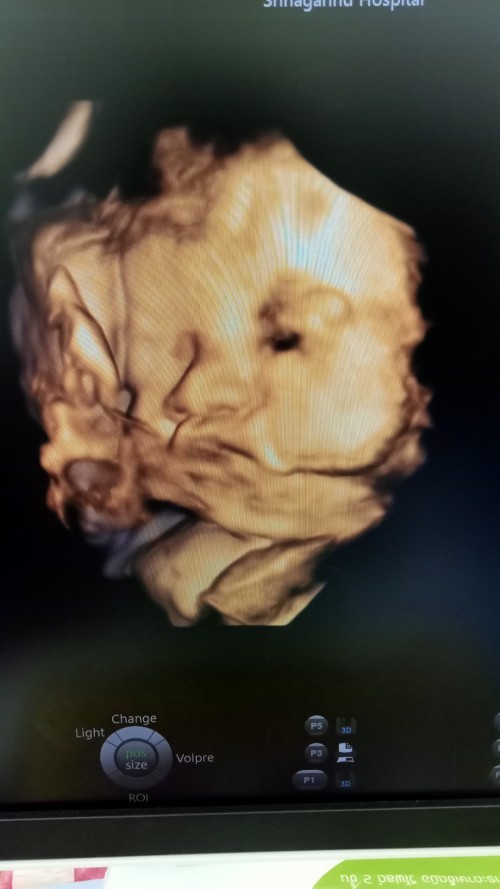

ภาพตอน 25w1d ค่ะ น้อนเป็นผู้ชายค่ะ 🥰